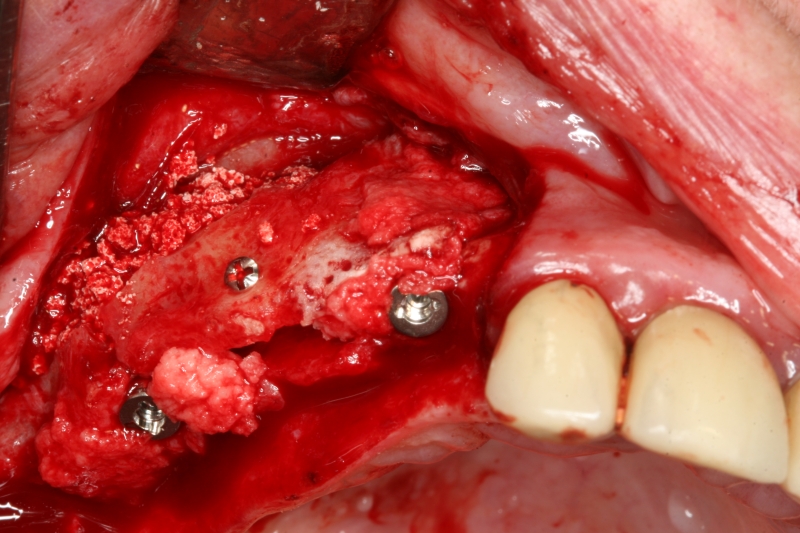

Implant insertion in atrophic alveolar ridge